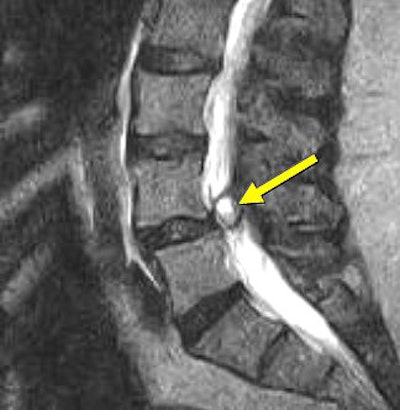

![]() |

| Above and below, left facet synovial cyst at L4-L5 (1.5 cm superoinferiorly by 1.1 cm anteroposteriorly by 0.8 cm transversely) under axial loading. This synovial cyst caused pronounced compromise of the left lateral recess with severe left lateral recess stenosis, as well as compression and anterior displacement of the left L5 descending nerve root as it exits the thecal sac. The left lateral thecal sac is compressed severely and displaced nearly to the midline. |